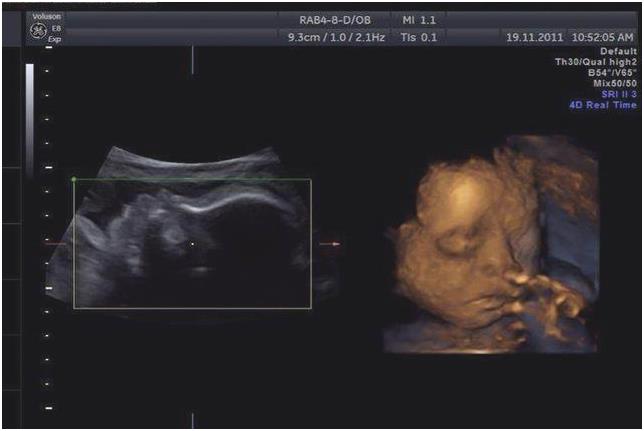

【温馨提示】第3次产检项目中最重要的是产科彩超筛查胎儿畸形,在孕期20-24周做超声波检查,主要是看胎儿外观发育上是否有较大问题。医生会仔细量胎儿是否有先天性异常。如果准妈妈照的是四维彩超,还可以看到宝宝的实时面部表情呢。照彩超之前,准妈妈要做的是保持平和的心态,如果过于紧张是会影响到胎儿的活动哦。